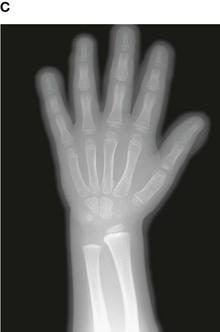

Up until the age of skeletal maturity, bony growth and development follows a typically predictable ordered state, which can be measured through either ultrasound, plain radiographs, or MRI scanning. Typically, the nondominant (left hand) is radiographed and is compared to a series of standard radiographs. From these images the bone age can be determined (Fig. 1.13).

image image image image image

Fig. 1.13 A developmental series of radiographs showing the progressive ossification of carpal (wrist) bones from 3(A) to 10(E) years of age.

In certain disease states, such as malnutrition and hypothyroidism, bony maturity may be slow. If the skeletal bone age is significantly reduced from the patient’s true age, treatment may be required.

In the healthy individual the bone age accurately represents the true age of the patient. This is important in determining the true age of the subject. This may also have medicolegal importance.